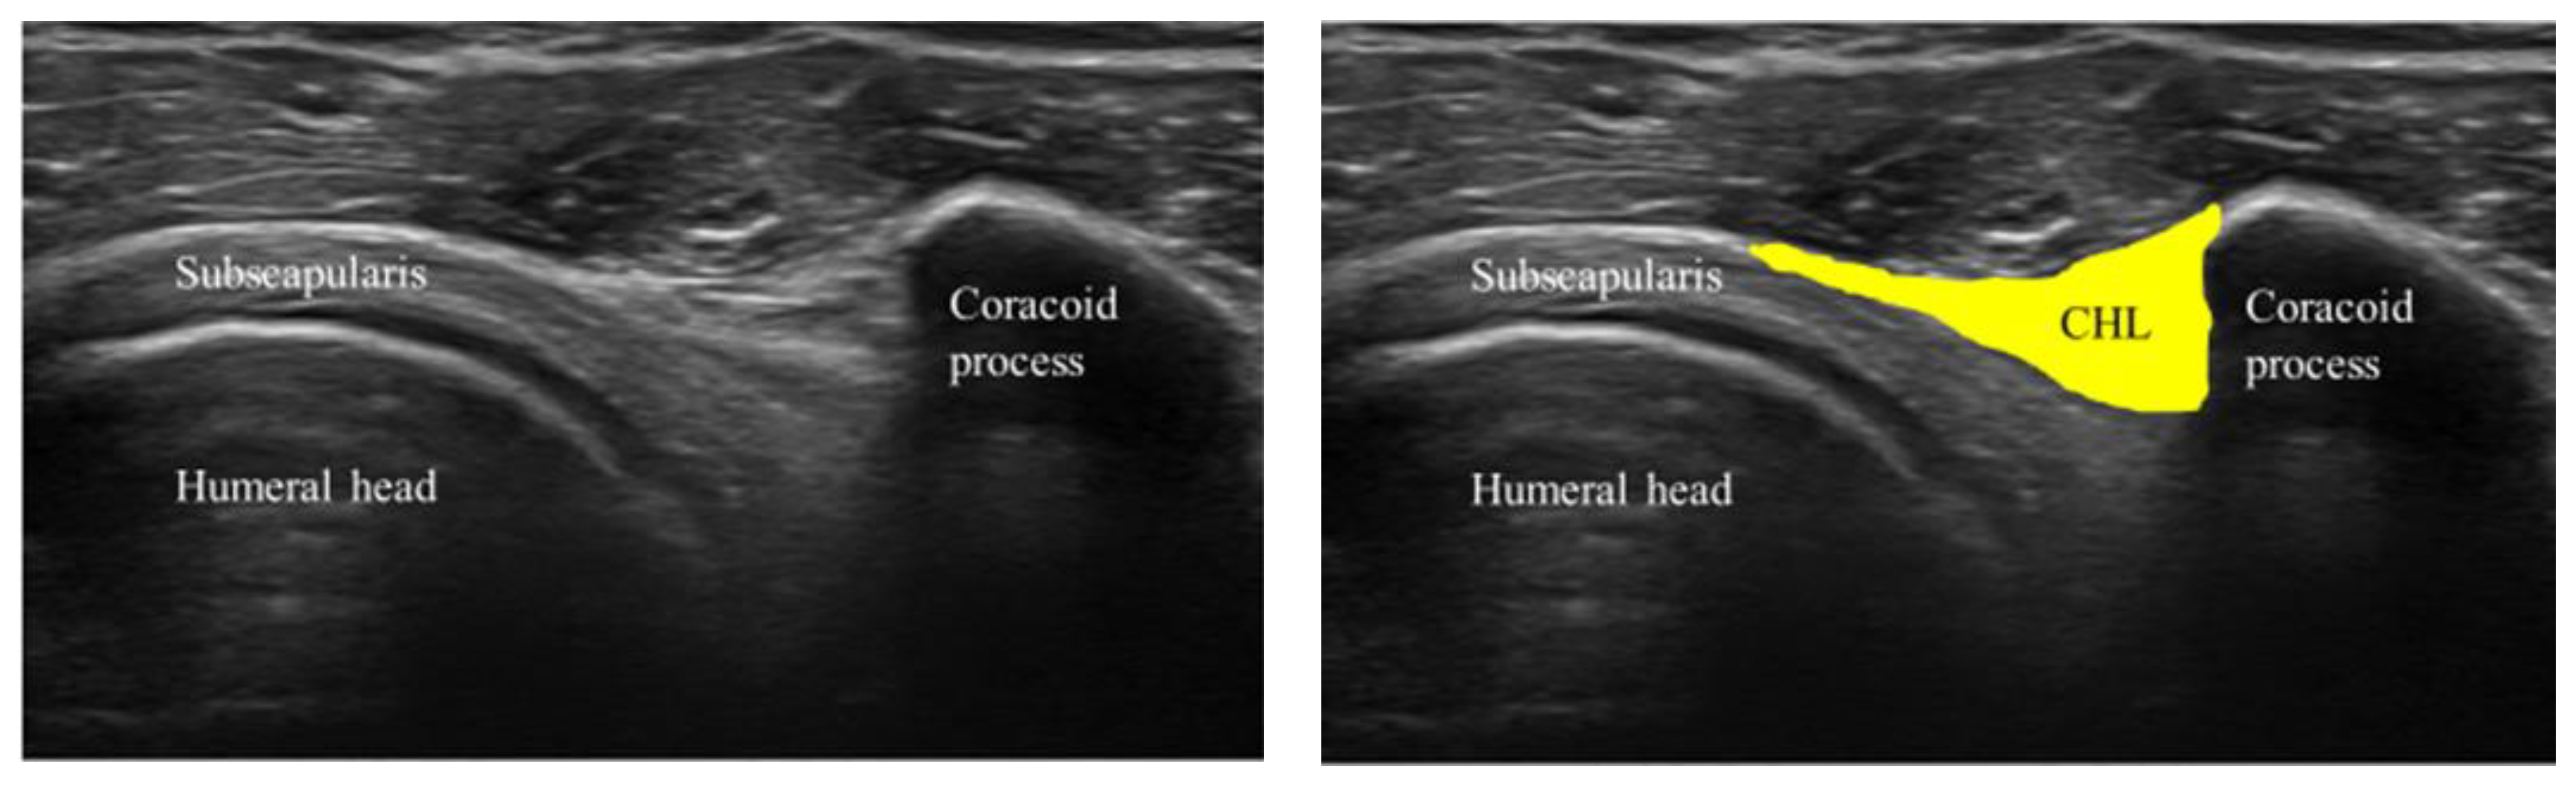

2.2. Experimental Data Acquisition and Analysis